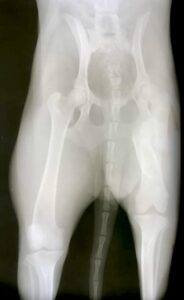

Maisey